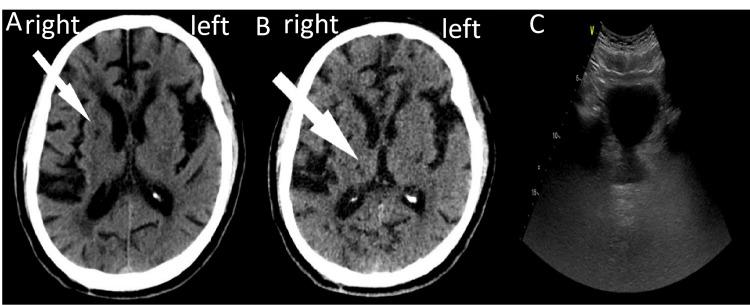

Neurogenic bladder (NB) is a frequently encountered post-stroke complication, characterized by symptoms, such as urinary incontinence, dysuria, increased frequency, and urgency. Here, we present a case of a 75-year-old male with urgent urination, frequent urination, urinary incontinence, conspicuous discomfort during urination, and an unpleasant smell in the urine following a stroke. By reviewing the patient's previous medical records of stroke and ruling out other potential causes for bladder dysfunction, a diagnosis of NB could be established. We implemented conventional physical therapy, pelvic floor muscle training with the electromyography biofeedback device, and continuous theta burst stimulation (cTBS) on the contralesional primary motor cortex area to manage bladder function. To the best of our knowledge, this is the first case report on cTBS applied to manage NB after stroke. Our treatment has demonstrated remarkable efficacy in enhancing bladder and kidney function, improving the overall quality of life, and alleviating anxiety and depression symptoms in this patient. This case study concludes that the noninvasive neuromodulation approach exhibits significant potential in the clinical field when addressing this specific patient population.

神经源性膀胱(NB)是一种常见的中风后并发症,其特征包括尿失禁、排尿困难、尿频和尿急等症状。在此,我们报告一例75岁男性病例,该患者中风后出现尿急、尿频、尿失禁、排尿时明显不适以及尿液有异味。通过查阅患者既往中风病史并排除膀胱功能障碍的其他潜在原因,可确诊为NB。我们采用了传统物理治疗、使用肌电图生物反馈设备进行盆底肌训练以及对健侧初级运动皮层区域进行连续theta爆发刺激(cTBS)来管理膀胱功能。据我们所知,这是首例关于应用cTBS治疗中风后NB的病例报告。我们的治疗在增强该患者的膀胱和肾脏功能、改善整体生活质量以及缓解焦虑和抑郁症状方面显示出显著疗效。本病例研究得出结论,这种非侵入性神经调节方法在针对这一特定患者群体时在临床领域具有巨大潜力。